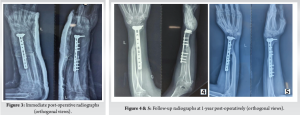

The patient was positioned supine after induction of general anesthesia and parts prepared and draped, and an incision was made on the dorsal aspect of the distal forearm and wrist centered over the 3rd metacarpal, the extensor retinaculum was incised, and a plane was made between the 2nd and 3rd extensor compartments. The tumor was excised along with the pseudo capsule and other unhealthy muscle, followed by extended curettage with phenol to sterilize the tumor bed. Insertion of the brachioradialis was spared. Ulnar osteotomy was planned after measuring the defect and the autograft was fixed to distal radius epiphysis with a 10 hole distal radius T plate and cortical screws followed by layered closure closely approximating the native anatomy followed by an above elbow plaster slab application kept for 2 weeks (Fig. 3), thereafter the sutures were removed and physiotherapy initiated with elbow flexion and extension, pronation and supination and grip strengthening exercises were initiated in a graded fashion.

The patient underwent regular clinical and radiographic monitoring for 1 year following the surgical intervention, with no evidence of recurrence during this period (Fig. 4 and 5). At the final follow-up appointment, the patient’s functional outcome was evaluated using the Musculoskeletal Tumor Society (MSTS) scoring system. This assessment tool considers both patient-specific factors, such as pain levels, functional capabilities, and emotional acceptance, as well as upper limb-specific factors, including hand positioning, lifting capacity, and manual dexterity. The child was followed up for a total period of 2 years, final dorsiflexion was 90°, palmar flexion was 35°, and pronosupination of 60° (Fig. 6). Grip strength was measured and compared with the contralateral side, measuring to be 68% of normal. At 2 years follow-up, the child scored 27 points in the MSTS score.